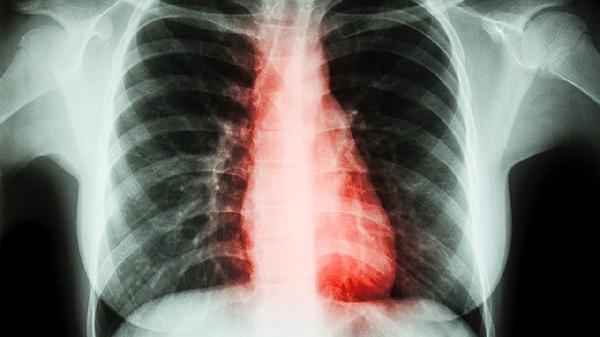

清肺散结丸含有多种具有清热解毒功效的中药成分,能够帮助清除体内的热毒,适用于因热毒内蕴引起的咳嗽、咽喉肿痛等症状。该药物通过抑制炎症反应,减轻肺部组织的炎症损伤,从而改善呼吸道症状。使用时应避免与其他寒凉性药物同时服用,以免加重脾胃负担。

清肺散结丸中的活血药物能够改善肺部微循环,促进淤血消散,适用于肺部瘀血引起的胸痛、咳血等症状。该功效对于肺纤维化、尘肺等慢性肺部疾病有一定辅助治疗作用。使用期间应避免剧烈运动,防止加重出血风险。